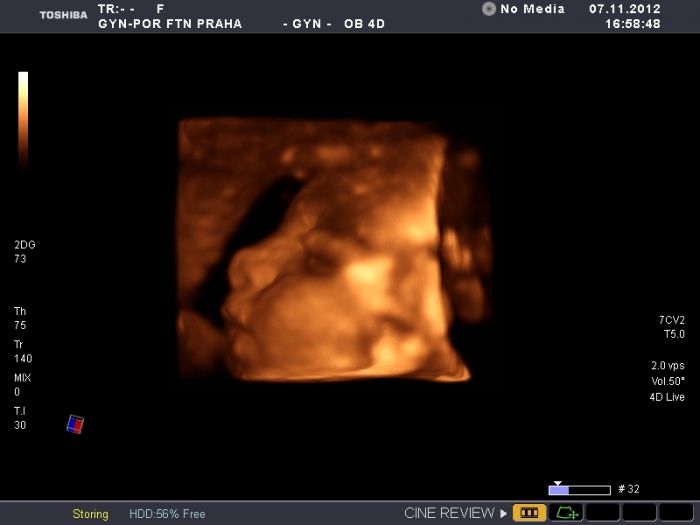

Holky, omlouvam se, ale tuhle fotku Vam musim proste poslat...pro predstavu, jak si ta nase mrnata v brisku krasne a spokojene hovi. Pohled zhora na mimco

Karimah, to je zázrak, viď!